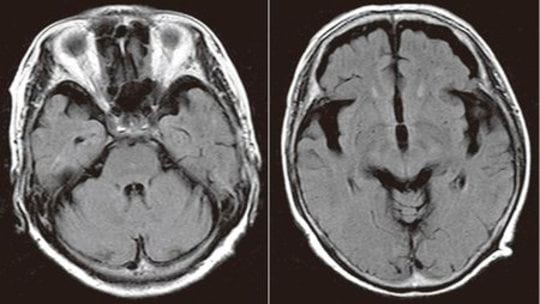

2年前から記憶があいまいに…60代女性のMRI画像

[図表1]前頭側頭型認知症のMRI像

※60代後半女性。2年前から記憶があいまいに。家事に無関心・無気力、肉じゃがを作れない。日にちが分からない。めまいがする。朝から起きていられない、ふらふらする。本やテレビを見ていると気分が悪くなってくる。HDS-R13点、MMSE13点。両側前頭葉および両側側頭葉の萎縮が目立つ。海馬の萎縮は認めない。